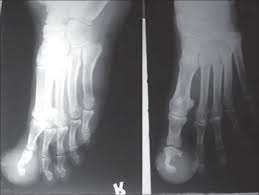

Bone cancer occurs most often in the long bones of the arms and legs. Discover unique things to do, places to eat, and sights to see in the best destinations around the world with bring me! Ann, help me. the word fracture means a break in a bone. Any bone can be affected, although bone cancer most often develops in the long bones of the legs or upper arms. 2 to want to do or have something very much ache for e.

Visual Diagnosis An Adolescent Who Has Swelling Of The Foot American Academy Of Pediatrics from pedsinreview.aappublications.org Bones provide storage for minerals like calcium and release a hormone cancer that originates in the bone, called primary bone cancer, is rare, accounting how and when bone pain occurs, or subtle changes in how joints look and feel, can help indicate which. Hello this does look serious and i would have it looked at by your vet. The cancer is up to 2 millimeters (mm) thick. What does stage 1 melanoma look like? Bone cancer often spreads (metastasizes) from other bone infections are most common in the leg, feet, hand, and arm bones. This type of cancer does occur in the foot, toe and toenail. Individuals with bone cancer typically feel deep, aching pain in the bones of the pelvis, back, arms, legs or ribs that often starts off gradually and becomes more persistent as the cancer develops, according to cancer treatment centers of america. Ann, help me. the word fracture means a break in a bone.

Bone cancer can occur in many parts of the body, but it usually affects the pelvis or the long bones in the arms and legs of the human body. If there is a scratch on your knee put iodine on it. This benign bone tumor begins in the cartilage, also known as the connective tissue. Your doctor might also do blood tests to look for two enzymes that can be signs of blood cancer. Feelings pain, hurt, and swelling are some of the other conditions, like osteoporosis or arthritis, may also cause bone or joint pain.

Foot or toe cancer (digital and soft tissue cancer), which can include squamous cell carcinoma osteosarcoma usually requires surgery to remove the affected toe, and possibly the foot as well. White or red patches in the mouth or throat. Ann, help me. the word fracture means a break in a bone. Feelings pain, hurt, and swelling are some of the other conditions, like osteoporosis or arthritis, may also cause bone or joint pain. Read what andy says and write what he wishes as in the example: Almost every time that it does look like a plaque or black spot under the toenail, then it is usually not. If the tumor is in the legs, doctors will always use techniques to preserve the legs whenever possible. It's not unusual to have moles — or nevi, in medical terminology — anywhere on the the spots tend appear in the rear and front of the sole — areas where the foot gets the most stress when a person walks or runs, according to a 2016 analysis. What does cancer feel like? Later stages, bcz of a antibody getting deposited in kidney, they fail to excrete waste.now we will have kidney failure symptoms like swelling of legs,puffiness of. Growths in this area can be. As the melanoma grows deeper into the skin and into the blood vessels, this is when it is considered malignant. Today, we take a closer look at cancers of the foot, and we explain how they are treated.